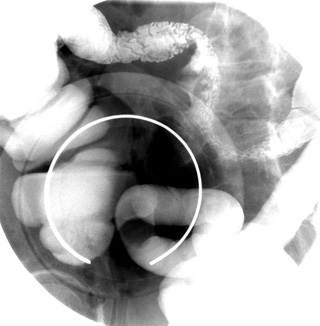

- When the cecum is well filled, perform graded compression

with the balloon paddle or F-Spoon to get good see-through penetration of

the barium.

- Take a spot image of the cecum in the RPO or supine position with

graded compression. When possible, also include the barium filled terminal

ileum.

NOTE: Complete cecal filling is

confirmed by identifying at least one of three landmarks: the appendix,

an appendiceal stump, or the ileocecal valve.